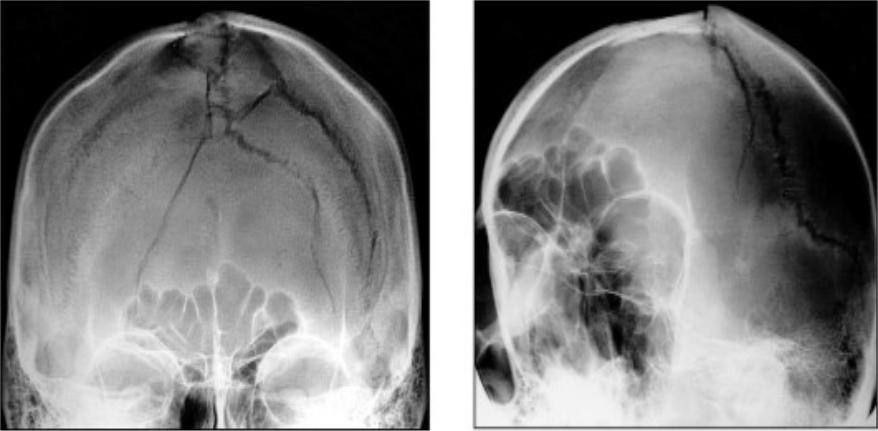

Вдавленные переломы свода черепа